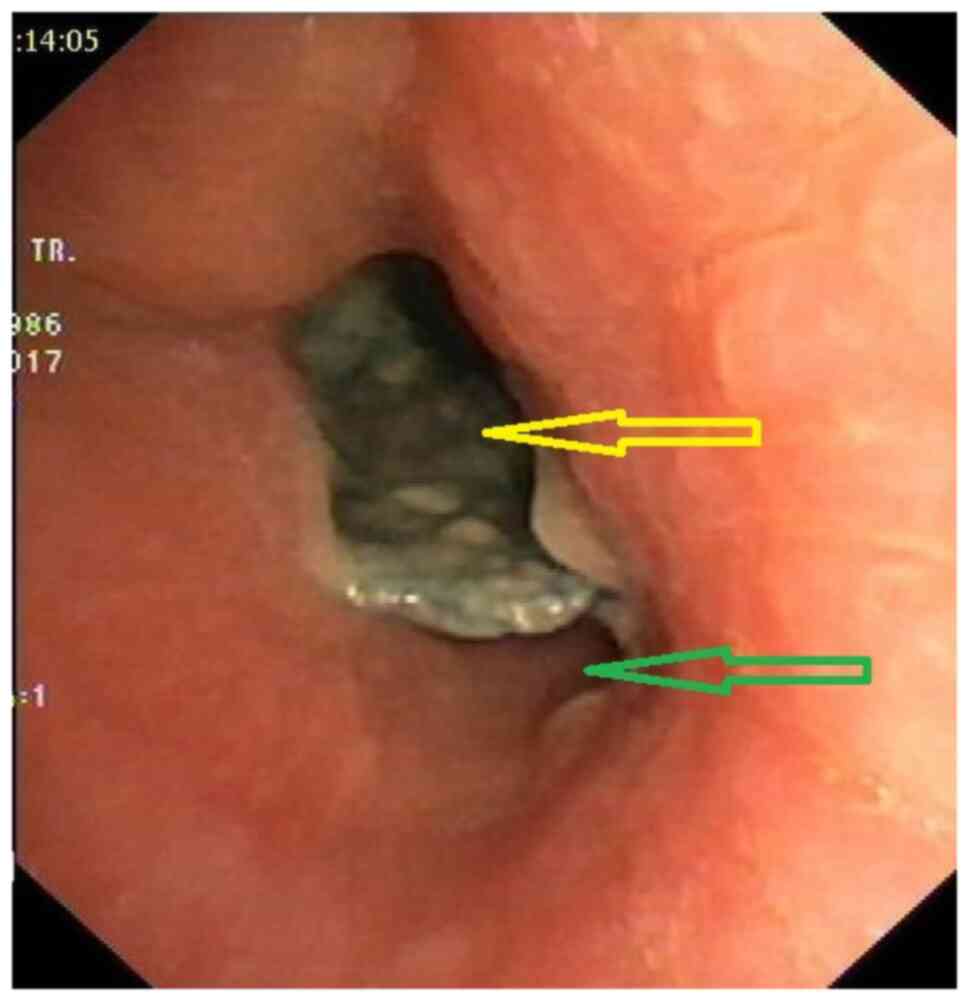

Acquired benign trachea‑oesophageal fistula is a rare benign pathological entity with varying aetiologies that most often occurs post‑intubation. This case report presents the case of a female patient, 31 years old, admitted to the emergency room with sepsis syndrome following bilateral aspiration pneumonia caused by a large trachea‑oesophageal fistula. The fistula was the result of intra‑tracheal migration of an oesophageal stent placed for post lye ingestion stenosis. Esophageal diversion and partial resection with oesophageal patch to repair the tracheal defect, under general anaesthesia with ventilation using rigid bronchoscopy and high frequency jet ventilation (HFJV), followed at a later date by esophageal replacement with colic graft were the procedures performed with a view to curing the patient. In conclusion, complex cases always require a tailored approach. It is important to note that HFJV may be applied for a longer period of time and the oesophagus can be used as patch for the posterior tracheal wall in selected cases. Staged surgery is also an option when the patients' poor health status does not permit major surgery.

Figure 4